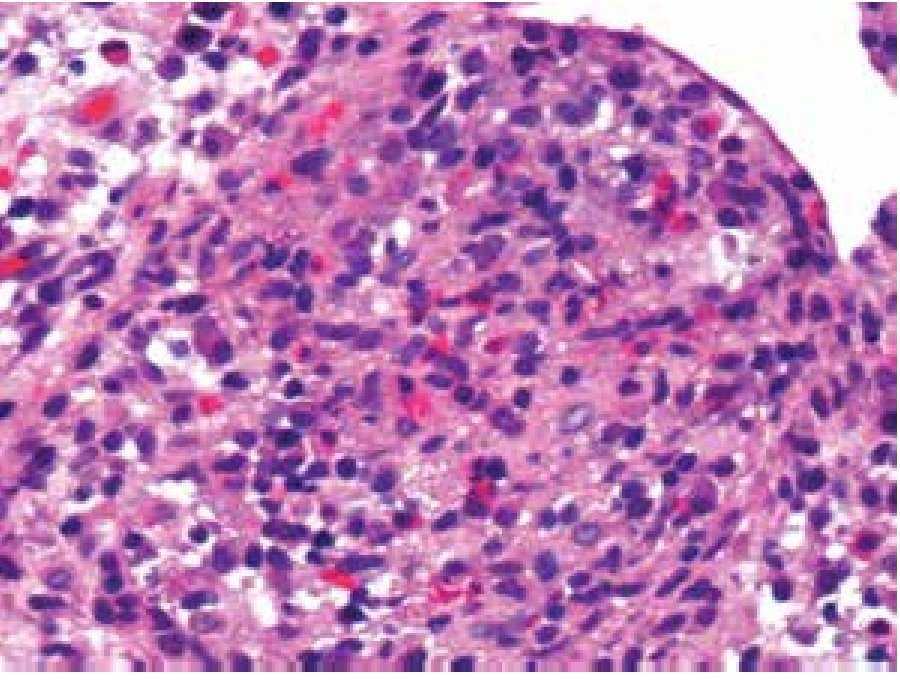

Paciente masculino de 28 años de edad, originario y residente de Chiapas, con un año de evolución, quien presentaba cuadros de estreñimiento y dolor abdominal ocasional, pérdida de peso de 7 Kg en seis meses, además de consumo de leche sin pasteurizar en dos ocasiones. Fue valorado por múltiples gastroenterólogos, se le realizaron estudios de endoscopia y colonoscopia, sin llegar a un diagnóstico preciso. Por nuevo cuadro de cuatro días de evacuaciones disminuidas en consistencia, 7/día, sin moco, ni sangre, con tenesmo y pujo tras la ingesta de cualquier alimento, dolor abdominal 9/10, asociado a náusea, sin vómito, con escalofríos y elevación térmica, acudió a Urgencias para valoración. En los estudios se evidenció hemoglobina de 12.3 g/dL, plaquetas 155 000 mm3 y VSG 35 mm/h. En TC se observó hepatoesplenomegalia, adenopatías y zonas de estenosis en íleon terminal (Figuras 1 y 2). Se realizó enteroscopia retrógrada de un solo balón, en donde se observaron úlceras lineales en íleon medio y terminal con engrosamiento de la mucosa y la válvula ileocecal con colon normal (Figura 3). La evaluación de patología mostró ileítis aguda ulcerada y crónica granulomatosa, asociada con micobacterias (Figuras 4, 5 y 6). El paciente se egresó del hospital para manejo ambulatorio con medicamentos antifímicos.

Figura 5. Lámina propia con nódulo linfohistiocítico rico en eosinófilos (H&E, 200X).